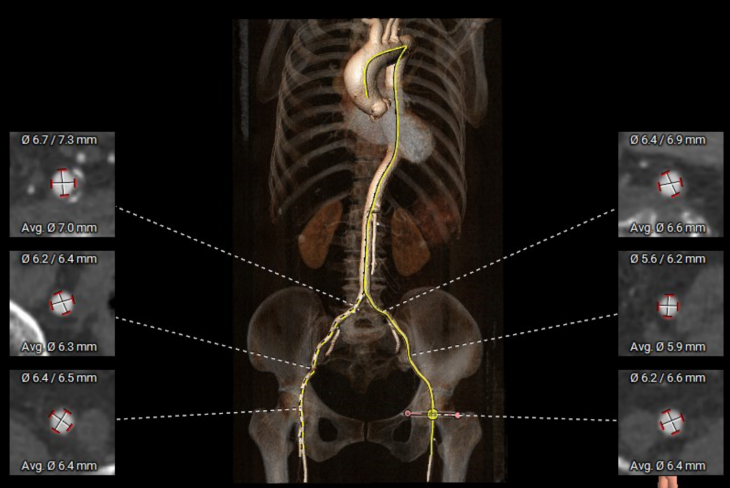

外周血管入路评估

5. 主动脉弓、右侧髂总动脉可见散在钙化斑块,双侧股动脉穿刺处未见明显迂曲、钙化、狭窄,入路血管内径尚可。

2. 冠脉开口高度尚可,左右冠瓣叶冗长,切线位左右冠瓣叶长度>>冠脉开口到瓣叶根部附着缘距离;冠脉未见明显钙化斑块;

3. 三窦大小不一,瓦氏窦、窦管交界内径偏小,升主动脉轻度扩张;左室腔内径尚可,心室壁未见明显增厚;

4. 瓣环水平夹角51°,主动脉弓夹角偏锐利,弓距偏小;